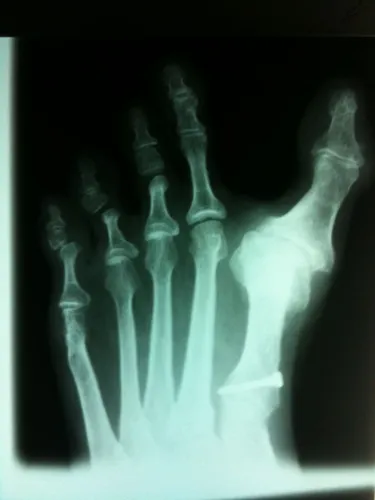

Before Surgery

The following radiograph depicst deviation of the great to away from the lesser toes created enlarged spacing between the great toe and second toe. This makes walking and use of shoegear difficult.

Avulsion Fracture of Lateral Collateral Ligament causing Hallux Varus, THe fractue can be seen to the right of the 1st metatarsal head.